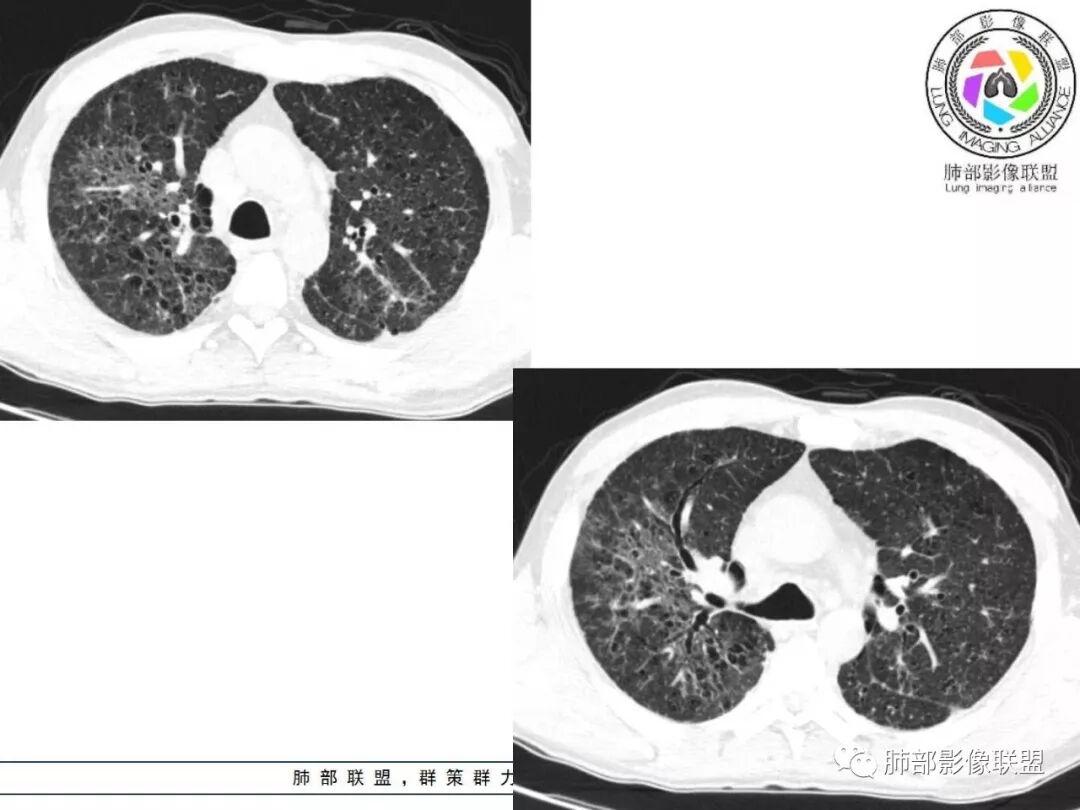

胸部CT:两肺弥漫病灶,磨玻璃影,少许实变,部分累及胸膜,磨玻璃区可见囊?少许胸腔积液,两肺可见结节,支气管血管束增粗,小叶间隔增厚,支气管走形有扭曲扩张,可见纤维化。气肿、大泡。考虑:感染性病变,PCP?查下HIV,CD4,G等。鉴别结核、结缔组织病肺浸润。

患者中年男性,发热1月,体温38℃-39℃,峰值40℃,无畏寒、寒战,伴黄痰,CRP升高明显,降钙素原稍升高,血沉、血糖正常。胸部CT:两肺弥漫病变,磨玻璃影+点片渗出,部分累及胸膜,磨玻璃区边界清楚,少许胸腔积液,两肺支气管血管束增粗,小叶间隔增厚,部分支气管走形有扭曲扩张,可见肺气肿、右肺尖肺大泡及部分纤维化改变。综合考虑:感染性病变。结核或PCP可能性大,鉴别风湿免疫、结缔组织疾病肺浸润和腺癌等恶性病变。

胸部CT:两肺弥漫病灶,中央间质分布为主,部分位于胸膜及叶间裂旁,磨玻璃影,斑片影,部分实性结节,肺气囊,支气管血管束增粗,小叶间隔增厚,叶间裂不均匀增厚,支气管走形有扭曲扩张,可见纤维化、气肿、大泡。考虑:LIP加MALT。鉴别PLCH、PCP、结核、结缔组织病肺浸润。

双肺弥漫性病变,多发磨玻璃密度及小叶间隔增厚,大部分沿支气管血管束分布,伴支气管轻度扩张,以午后及晚上发热为主,考虑感染性病变,间质性结核可能大,另双肺多发肺气囊,LIP待排

双肺病灶,以间质性病灶为主,支气管壁增厚,可见树芽征改变,考虑感染性病变,间质性结核可能。

病灶呈片状磨玻璃密度影,呈典型的烟花征。磨玻璃影密度偏高,有网结节样改变,与正常肺实质分界清楚,且常见相对高密度的勾画。

烟花征分为3肿类型:晕征、反晕征及均匀分布。

病变一般沿血管支气管束分布或小叶分布,一般上肺多于下肺(这与常见继发性肺结核分布相若)。

常会伴有其他继发性肺结核病灶,如斑片影、结节影,树芽征,新旧不等改变。

2. 肺气肿背景(小叶中心性肺气肿);双肺多发病灶整体沿血管支气管束及胸膜下分布,以上叶及下叶背段分布为主,有实变及GGO,边界清楚,有树芽,小叶间隔及中央间质增厚,叶间裂见到多发结节,部分支气管不规则牵拉扩张,提示病灶纤维化明显,结合临床病史,考虑病灶为间质性感染,肺门及纵隔内有钙化淋巴结,小叶间隔结节,考虑淋巴道增值性疾病可能,综合常规要怀疑间质性肺结核。